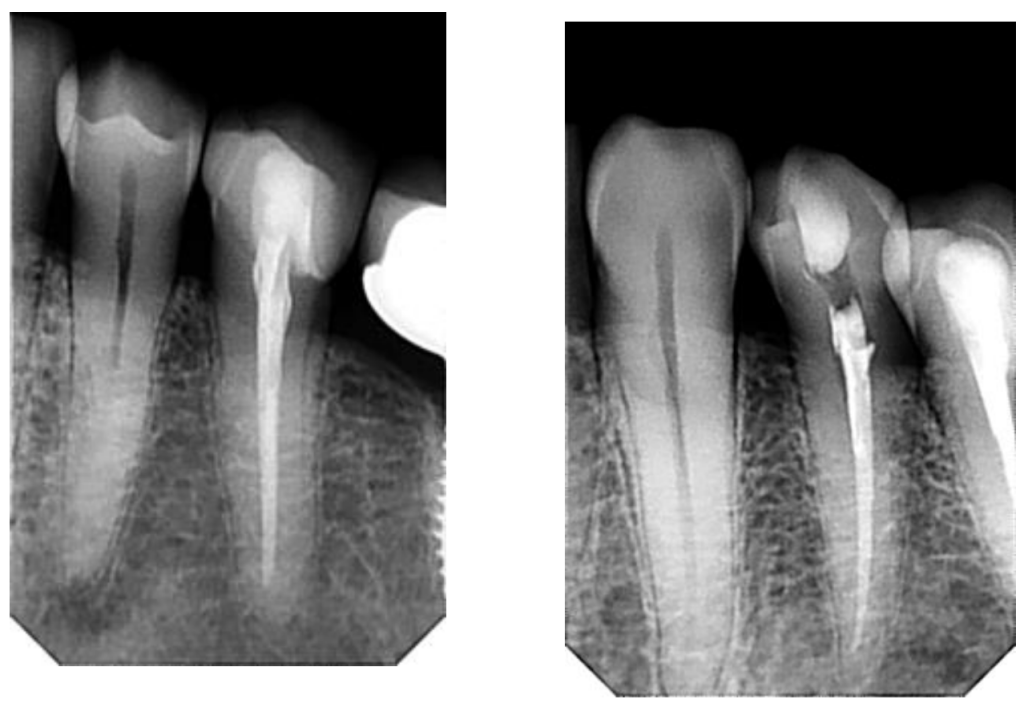

Case Study: Endodontics - Root Canal Therapy

Before: The patient presented with symptomatic apical periodontitis, showing infection at the root tip and discomfort when chewing. Radiographic analysis confirmed the need for endodontic treatment to eliminate the infection and preserve the tooth.

Treatment: Root canal therapy was carried out using modern techniques, including advanced rotary instrumentation (WaveOne Gold), active irrigation solutions (NaOCl, EDTA), and biocompatible sealing with AH Plus resin. This ensured complete cleaning, disinfection, and sealing of the canals.

After: The final radiograph demonstrates a properly sealed root canal, elimination of the infected tissue, and restoration of tooth stability. The treatment successfully relieved pain, saved the natural tooth, and protected the patient from future complications.

Before: The patient was diagnosed with asymptomatic irreversible pulpitis in a lower molar. Although pain was not acute at the moment, radiographic evaluation confirmed irreversible inflammation of the pulp tissue, requiring endodontic treatment to prevent infection and tooth loss.

Treatment: Root canal therapy was performed using advanced rotary instrumentation (WaveOne Gold system), active irrigation with NaOCl and EDTA, and precise obturation with AH Plus resin. The procedure ensured thorough cleaning, shaping, and sealing of the root canals.

After: The final radiograph shows a well-sealed root canal system with complete disinfection. The tooth was preserved, stabilized, and restored to full function, preventing future complications and eliminating the risk of infection.